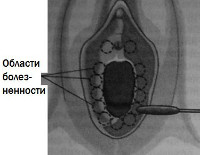

• Тест с ватной палочкой. При прикосновении аппликатора с ватным наконечником к мягким тканям преддверия выявляются участки с повышенной болевой чувствительностью.